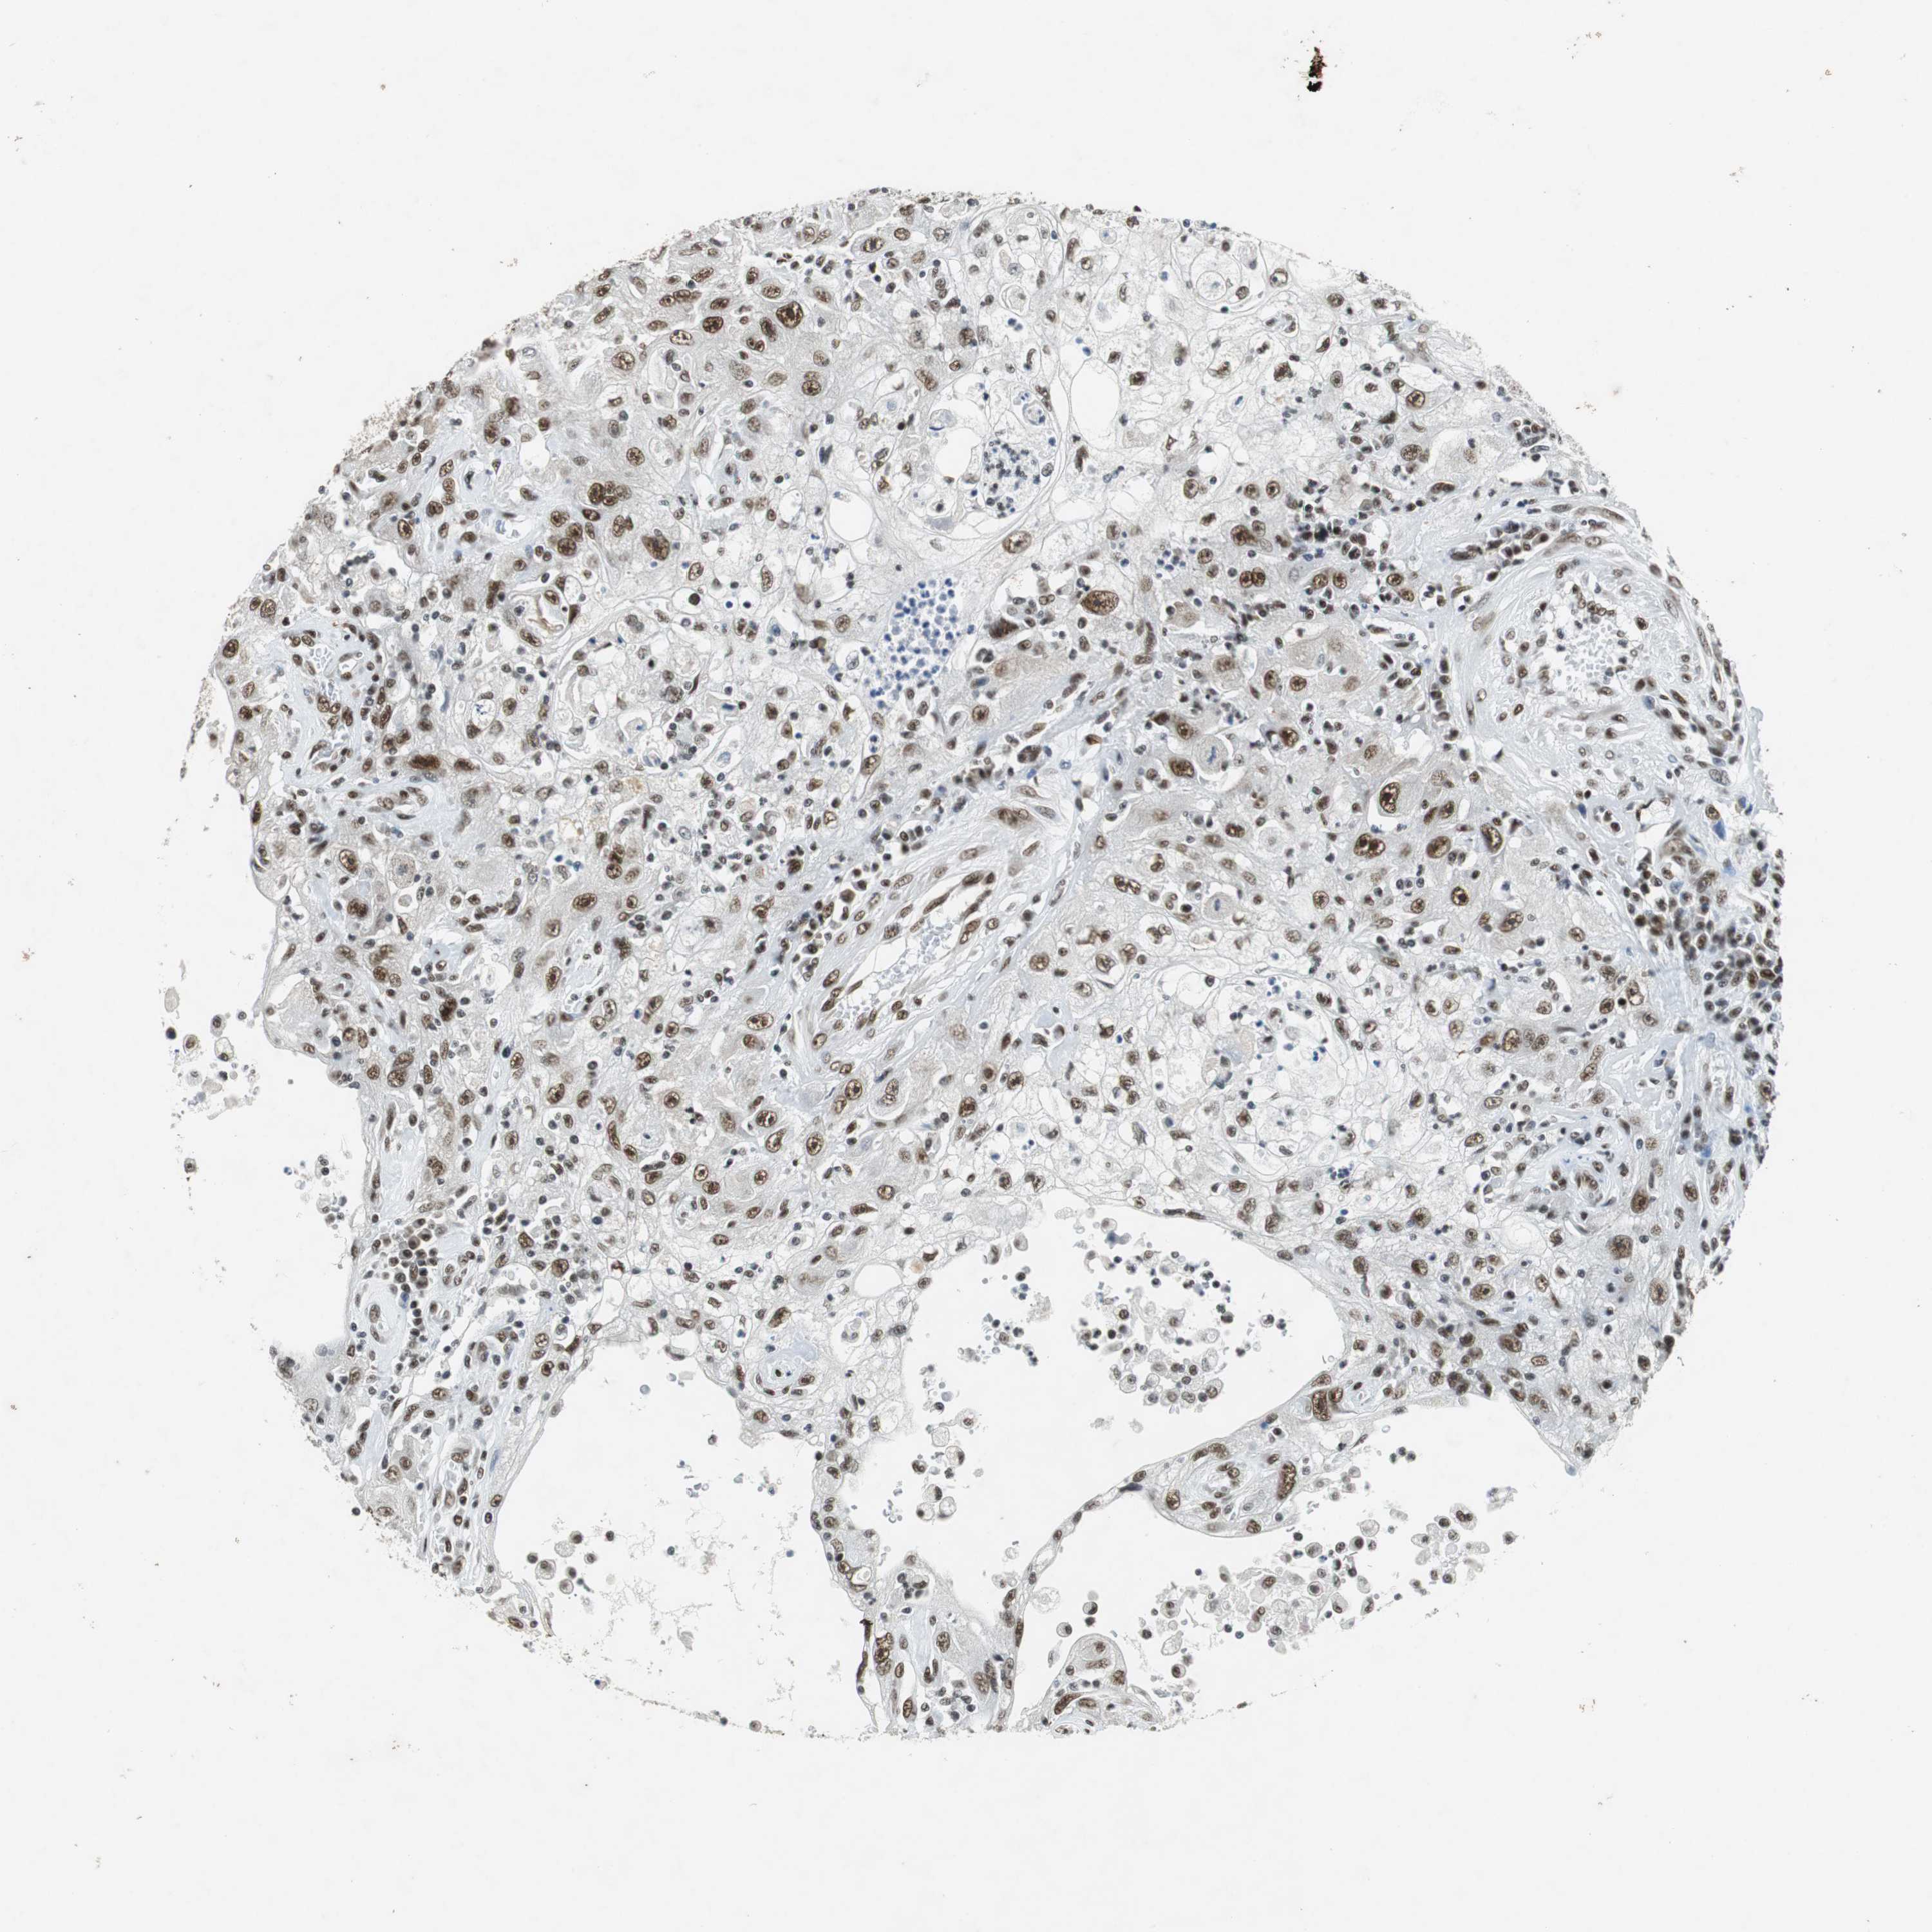

CANCER SKIN CANCER Show tissue menu

Basal cell and squamous cell cancer

SKIN CANCER - Protein expressioni

A mouse-over function shows sample information and annotation data. Click on an image to view it in a full screen mode. Samples can be filtered based on level of antibody staining by selecting one or several of the following categories: high, medium, low and not detected. The assay and annotation is described here.

Each image is clickable and will lead to virtual microscopy that enables deeper exploration of all samples and also displays staining intensity scores, fraction scores and subcellular localization as well as patient and tissue information for each sample.

Antibody HPA035174

Basal cell carcinoma

Squamous cell carcinoma, NOS